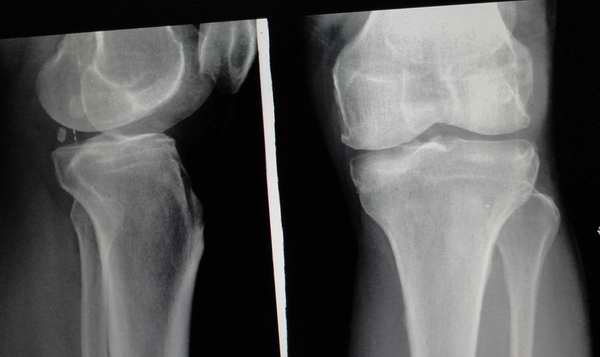

标题: 第二例病人,外伤线上的是不是平台陈旧性骨折

2、感觉不像平台的陈旧骨折。

第二例:膝关节退行性改变;不排除内侧平台陈旧性骨折。

第二位病人,内侧平台陈旧性压缩骨折可能性大,建议ct。

第二例考虑退行性改变。

第一个病例报告时要提示膝关节间隙馁窄外宽改变,建议结合临床或进一步检查,第二个病例支持考虑胫骨平台骨折后改变。

第一例可报:内窄外宽改变,建议mri检查。第二例考虑有胫骨平台陈旧性骨折